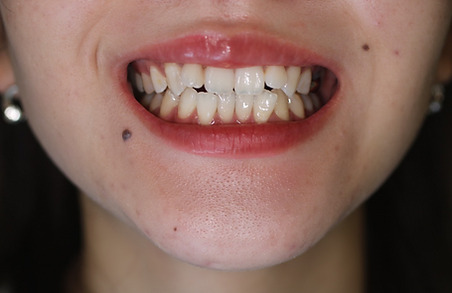

1矯正・マウスピース【治療例1】

治療前